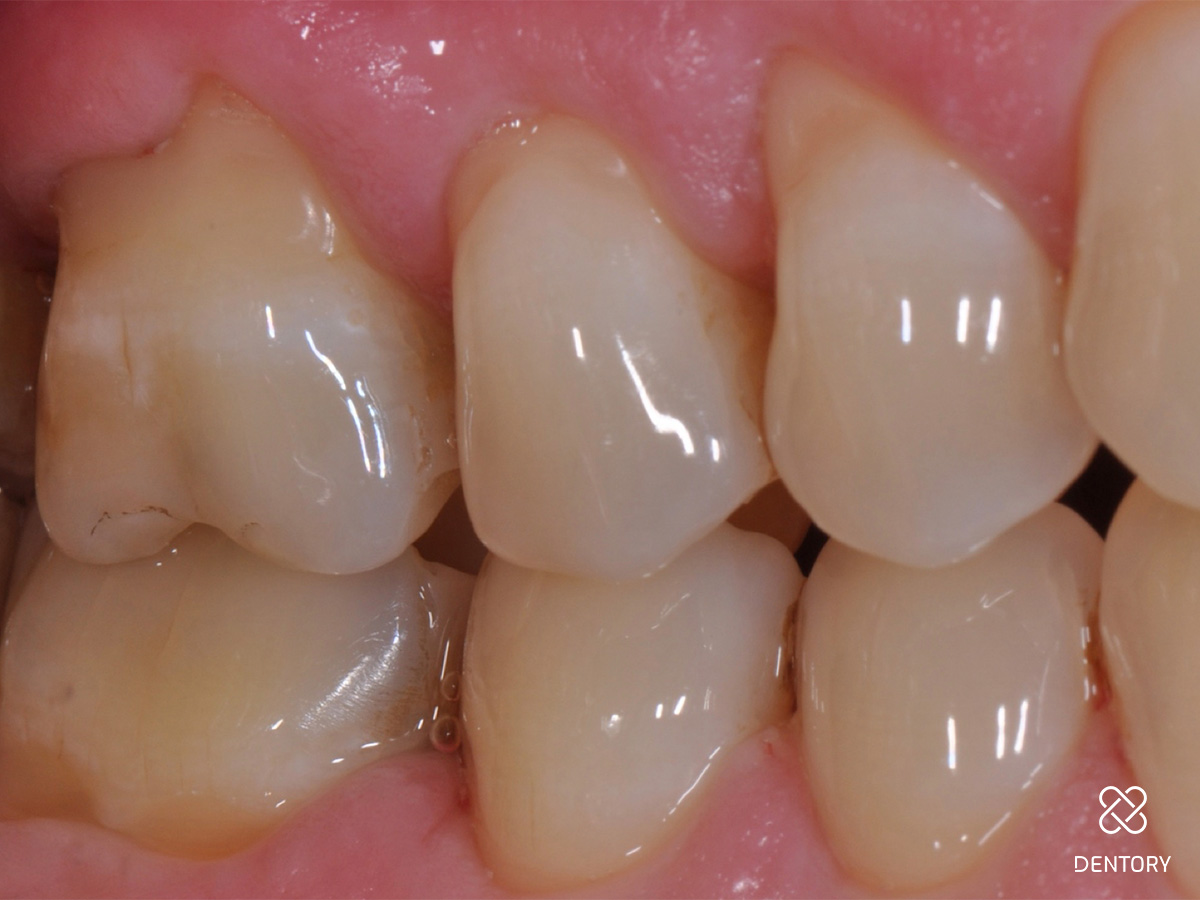

Abbildung 2

Die Ausgangssituation der regio 16/17. Hier wurden initial Sondierungstiefen von 9 und 11 mm mesial an Zahn 17 gemessen.

Abbildung 16

Die klinische Situation regio 16/17 sechs Monate nach Eingriff zeigt ein gesunde und stabile Gingivaverhältnisse.